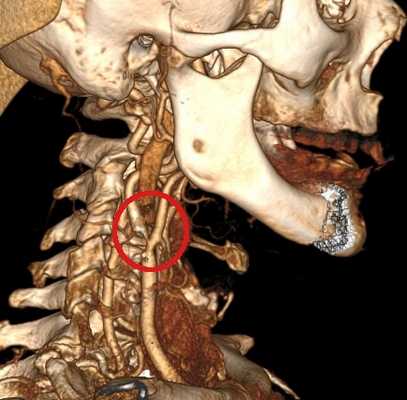

![Аномалия Киммерли]()

Аномалия Киммерли

Патологическая костная дужка на 1 шейном позвонке. Позвоночная артерия проходит через узкое костное отверстие перед входом в череп. В ряде случаев её компрессия может вызывать синдром позвоночной артерии с мучительными жалобами. На фотографии показана эта аномалия, выявленная при обследовании.